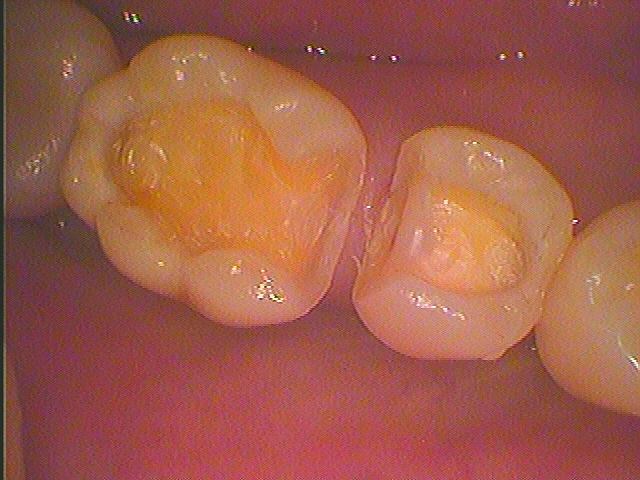

銀歯を白くしたいとのこと。| |広島市安佐南区の歯科医院 銀歯を白くしたいとのこと。 トップ お知らせ・ブログ 銀歯を白くしたいとのこと。 銀歯を白くしたいとのこと。 Web診療予約 初めての方へ 選ばれ続ける理由 院内設備について 歯が痛いしみる一般歯科 歯がぐらぐらする歯周病 健康な歯を保ちたい予防歯科 子供の虫歯予防をしたい小児歯科 銀歯をセラミックに審美歯科 白い歯を目指しませんか?ホワイトニング 矯正専門医がいるので安心矯正歯科 抜けた歯を補いたいインプラント・入れ歯 医院案内 スタッフ紹介 メリィハウス歯科クリニックオフィシャルホームページ ラベンダー歯科クリニックオフィシャルホームページ お知らせ・ブログ ホーム 診療科目 一般歯科 歯周病治療 予防治療 小児歯科 審美治療 ホワイトニング 矯正歯科 入れ歯・インプラント マウスピース矯正 初めての方へ 院長・スタッフ 設備紹介 医院案内・アクセス メニューを閉じる